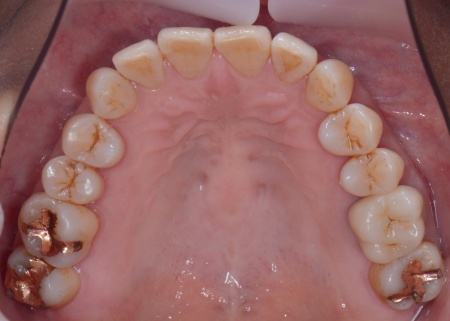

さらに虫歯が再発していた左上奥歯については、虫歯をしっかりと取り除いたうえで被せ物による修復治療を提案しました。 それぞれのメリット・デメリットを丁寧に説明したところ、治療計画に同意いただきました。 まず、歯周基本治療から開始しました。 下左右の第1大臼歯を抜歯し、その部位にインプラントを埋め込む手術を行いました。同時に、インプラントの隣にある下の第2大臼歯に対して歯周組織再生療法を施しています。 また、左上の奥歯は虫歯を取り除いたあと、歯の形を整えて型取りを行い、最終的にジルコニアクラウンを装着しています。 段階的に治療を進め、すべての治療を終了しました。 |

| 費用 | 約1,930,000円 【内訳】 歯周組織再生療法4ヶ所、インプラント2本、角化歯肉移植、ジルコニアクラウン |